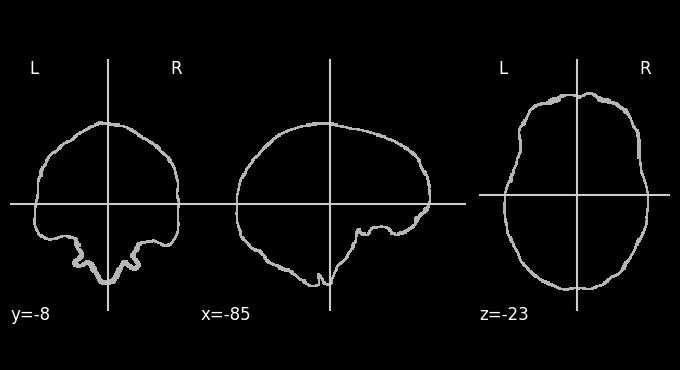

Since fMRI studies focus on brain tissue, our first step is to remove the skull and non-brain areas from the image.

Brain Extraction#